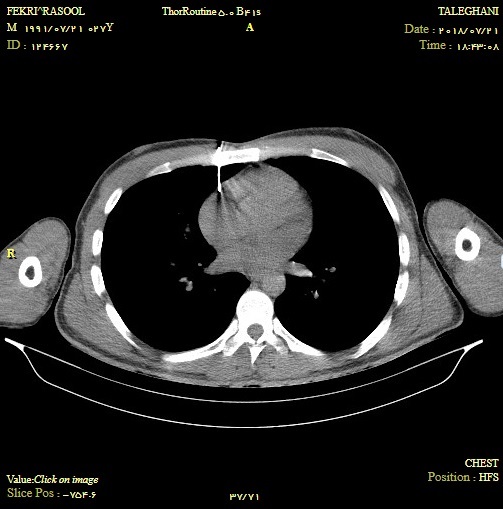

در لحظات غروب آفتاب شنبه 30 تیر ماه طلوع دوباره زندگی کارگر مشهدی به دست متخصصین بیمارستان طالقانی روشنی بخش شد. بدنبال حادثه برخورد میخ پرچ با قفسه سینه این کارگر قطعه ای از این میخ تا قلب نفوذ کرده و به لایه پریکارد رسیده و باعث تامپوناد قلبی و خونریزی دور قلب شده بود. وی بلافاصله پس از رسیدن به اورژانس بیمارستان طالقانی تحت معاینه و سپس سی تی اسکن قرار گرفت و محل جسم خارجی مشخص گردید. به دلیل خونریزی دور بافت قلب ، فعالیت آن دچار اختلال گردیده بود که بلافاصله با پریکاردیوسنتز تحت گاید سونو توسط متخصصین طب اورژانس و جراحی مقداری از خون تخلیه شد و امکان انتقال فوری بیمار فراهم گردید. عمل جراحی بیمار توسط دکتر جمعه زاده متخصص جراحی عمومی با موفقیت انجام شد و بیمار به بخش مراقبت های ویژه منتقل گردید. |